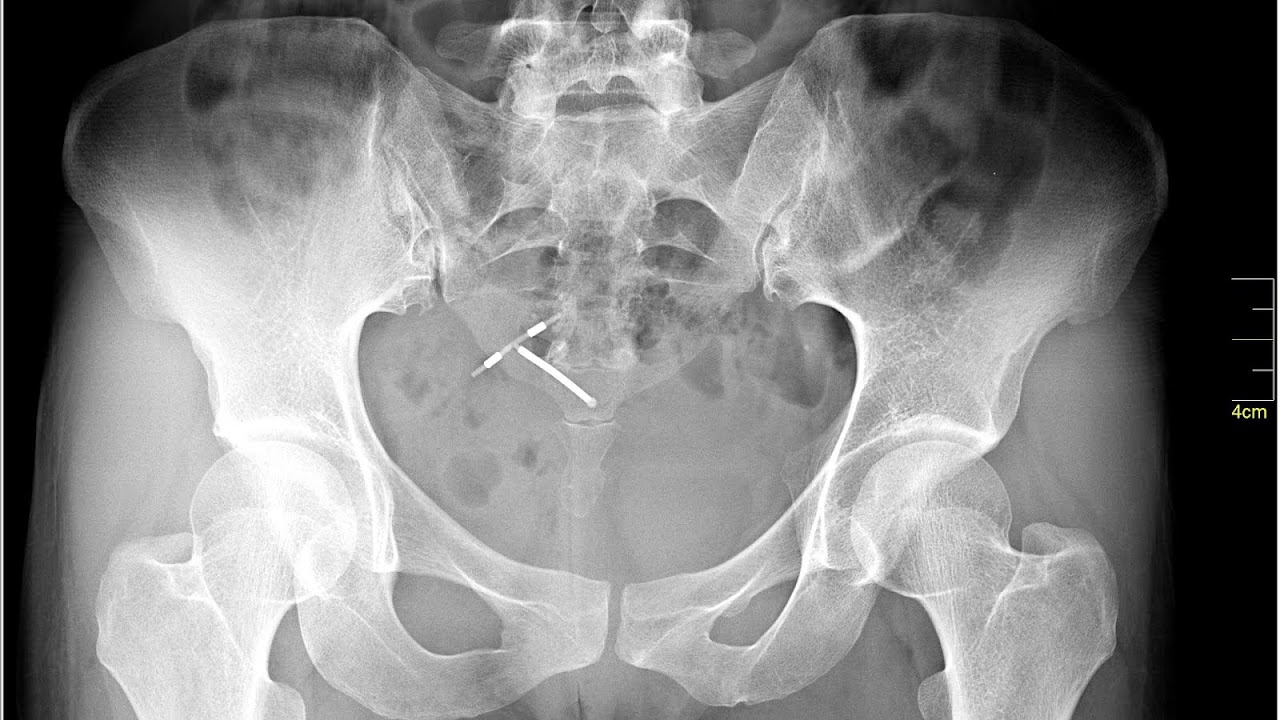

- Perforation: Very rarely, the IUD can be pushed through the wall of the uterus during insertion. Risk of perforation is mostly determined by the skill of the practitioner performing the insertion. For experienced medical practitioners, the risk of perforation is 1 per 1,000 insertions or less. With postpartum insertions, perforation of the uterus is more likely to occur when uterine involution is incomplete; involution usually completes by 4-6 weeks postpartum. Special considerations apply to women who plan to breastfeed. If perforation does occur it can damage the internal organs, and in some cases surgery is needed to remove the IUD.

- A "lost coil" occurs when the thread cannot be felt by a woman on routine checking and is not seen on speculum examination. Various thread collector devices or simple forceps may then be used to try to grasp the device through the cervix. In the rare cases when this is unsuccessful, an ultrasound scan may be arranged to check the position of the coil and exclude its perforation through into the abdominal cavity or its unrecognised previous expulsion.